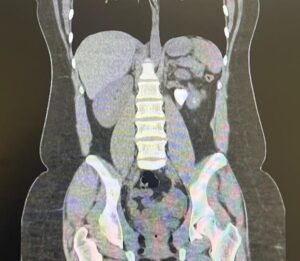

Paciente do sexo feminino, branca, 28 anos comparece ao consultório de especialidade encaminhada após diagnóstico e tratamento de quadro de cistite feito atendimento de emergência com achado em exame de imagem (mostrado abaixo). Foi iniciado tratamento com cefuroxima (500 mg de 12/12h por 5 dias). Negou febre, calafrios, hematúria, disúria, outras infecções do trato urinário (ITU). Refere passado de litíase urinária na infância com necessidade de algumas intervenções, dentre elas: 04 litotripsias extracorpóreas por ondas de choque (LEOC) à esquerda e 02 ureterorrenolitotripsias flexíveis a laser bilaterais.

Exames laboratoriais da emergência mostram leucocitose sem desvio, função renal preservada e discreto aumento de PCR. EAS com piúria e hematúria microscópica.

ACálculo renal coraliforme completo e indicação de ureterorrenolitotripsia flexível associada a nefrolitotripsia percutânea (terapia combinada).

DCálculo renal coraliforme completo e indicação de nefrolitotripsia percutânea (NLPC).